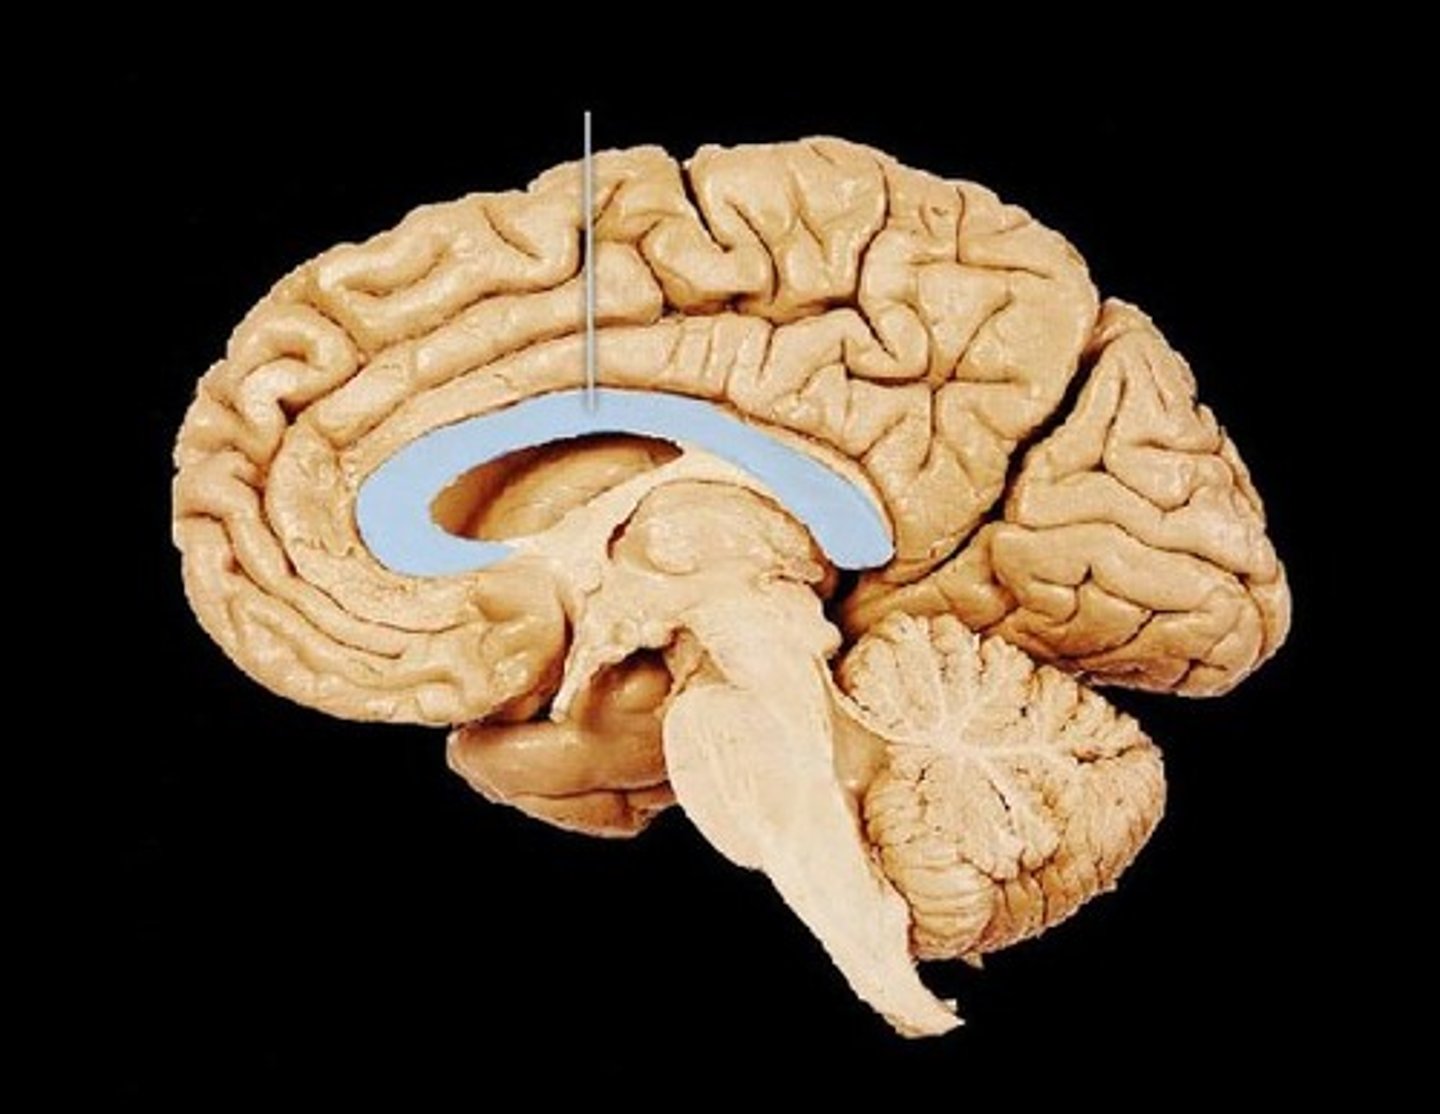

corpus callosum

lateral ventricles